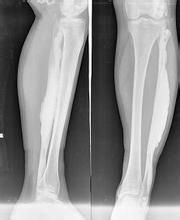

蠟油樣骨病從X線平片看出,蠟油樣骨病患者的髖部主要表現為一側髖關節兩端骨質增生硬化,呈斑片狀或團塊狀高密度影,病變可跨越髖關節.但關節腔及關節面保持正常,髖關節周圍軟組織口見異位骨化。表現為骨內有斑點狀或條紋狀緻密影,不易引起輪廓改變,關節多不受影響,即使關節兩端骨質發生明顯新骨堆積,關節面仍保持光滑,附近軟組織中常有骨質沉積。